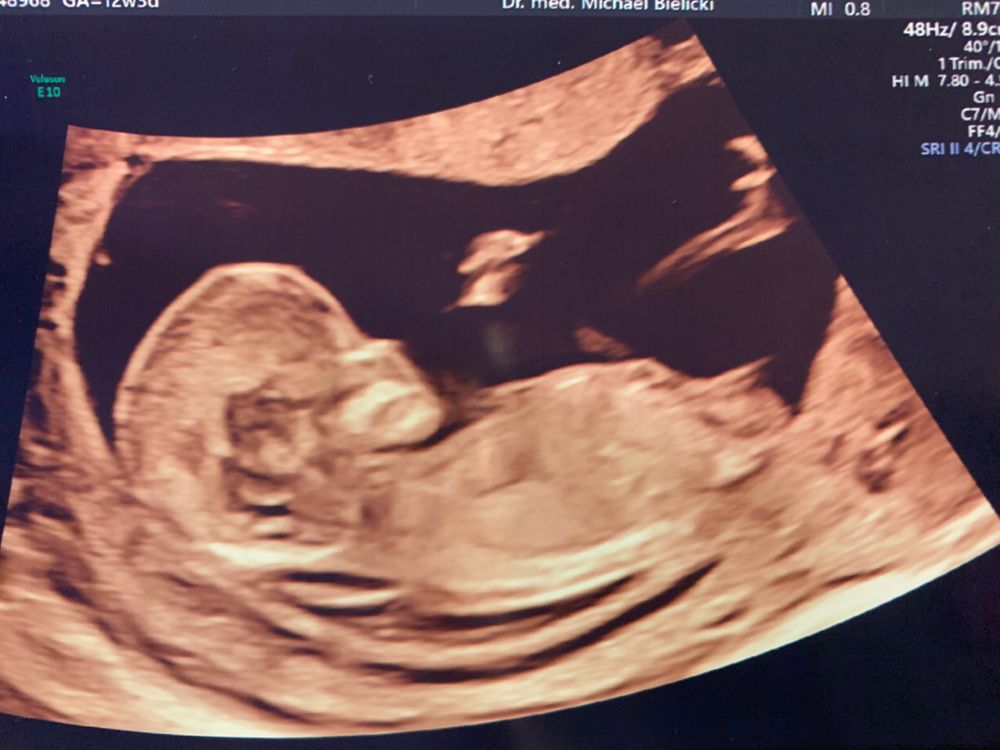

Ну девчуля же, да?😻

Если то что я вижу не 3 фото, это девочка 👧

Лёся, добавила ещё одну фотку с другого ракурса. Посмотри, может, сейчас разглядишь😀 да, нипт сдала. Результат через неделю.

Сентябринхен, если это половой бугорок, то прям 99,9999% девочка. Но только если это половой бугорок 🤣 потому что на бедровую кость тоже похоже. Но у Леи тоже на сроке 11-12 недель было точно такое же узи и в итоге девочка. Я даже на бб свои предположения писала. Так что я тоже за девочку!

Я вот тоже по профилю поняла, что девчоночка, она была такая изящная😍, как и сейчас))) Думаю сердце вам и так все уже сказало 💕

Евгения, наверное, да. Как профиль увидела, уже даже и не вглядывалась в подробности🥰

Валерия, скажем так, сегодня на узи на миг включили область между ног и там было совсем не так все очевидно, как у сына. Плюс скорее вопрос про общую конституцию и профиль. На сравнении с сыном мне кажется очень аккуратным

Ирина, определяют на таком сроке тоже, но достоверность спорная)

Алина М, снизу на таком сроке не смотрят. Там нет половых органов, а только половой бугорок, который в профиль как раз и смотрят.